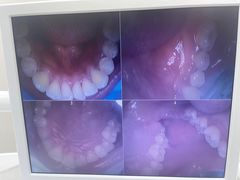

• 牙博士口腔品牌连锁(杨浦店)

• -牙博士口腔品牌连锁(杨浦店)

恩俊 | 24-04-22

smilezoro | 24-04-22